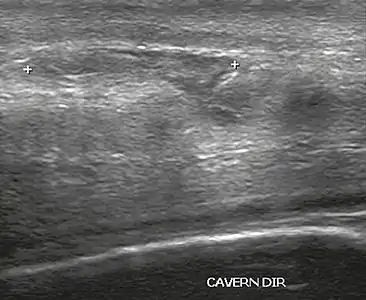

Ultrasound examination is able to depict the tunica albuginea tear in the majority of cases (as a hypoechoic discontinuity in the normally echogenic tunica). In a study on 25 patients, Zare Mehrjardi et al. concluded that ultrasound is unable to find the tear just when it is located at the penile base. In their study magnetic resonance imaging (MRI) accurately diagnosed all of the tears (as a discontinuity in the normally low signal tunica on both T1- and T2-weighted sequences). They concluded that ultrasound should be considered as the initial imaging method, and MRI can be helpful in cases that ultrasound does not depict any tear but clinical suspicions for fracture are still high. In the same study, authors investigated accuracy of ultrasound and MRI for determining the tear location (mapping of fracture) in order to perform a tailored surgical repair. MRI was more accurate than ultrasound for this purpose, but ultrasound mapping was well correlated with surgical results in cases where the tear was clearly visualized on ultrasound exam.[10] The advantage of ultrasound in the diagnosis of penile fracture is unrivaled when its noninvasive, cost-effective, and nonionising nature are considered.[11]

In the ultrasound examination, a lesion of the tunica albuginea presents as an interruption in (loss of continuity of) the echoic line representing it (Figure 4). Small, moderate, or broad hematomas demonstrate the extent of that discontinuity. Intracavernous hematomas, sometimes without the presence of a tunica albuginea fracture, can be observed when there is a lesion of the smooth muscle of the trabeculae surrounding the sinusoid spaces or the subtunical venular plexus.[2]

Figure 4 A: Ultrasound of the penis, right lateral view. Longitudinal section showing rupture of the tunica albuginea with an adjacent 1.92 cm hematoma (between calipers), due to trauma.[2]